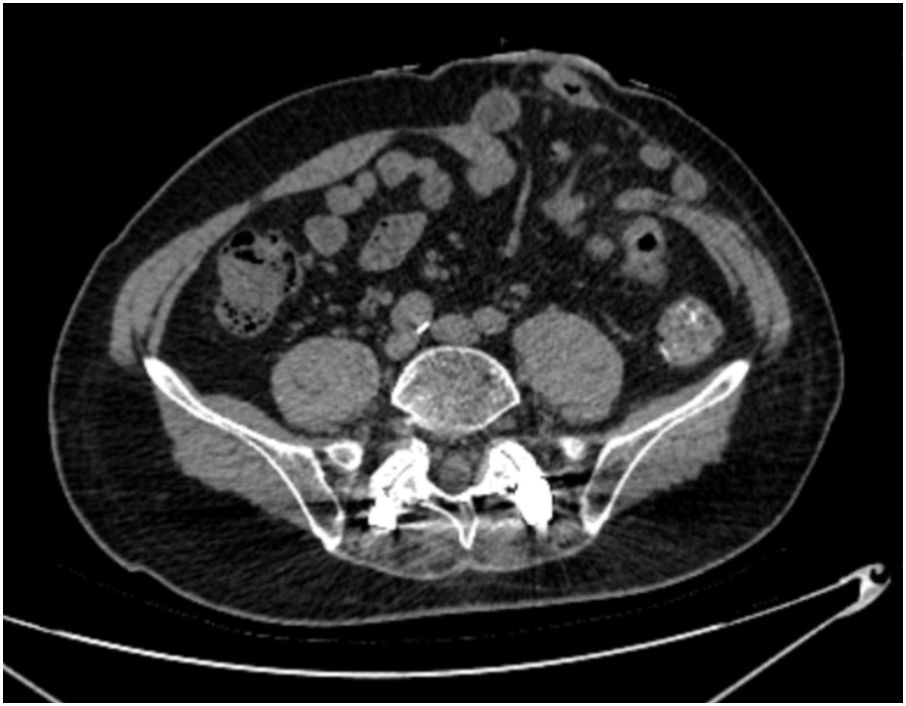

PSH was diagnosed by physical examination and abdominal CT following the 2023 European Society of Hernia guidelines (19), which was defined as an incisional hernia occurring at or adjacent to the end colostomy, with the hernia sac containing the omentum, small bowel, colon, or a combination thereof (Figure 2). Postoperative examinations were performed according to the international guidelines, including physical examinations every 3 months and abdominal CT every 6 months during the first 2 years, followed by examinations every 12 months for the subsequent 5 years. The final follow-up date for all cases was June 30, 2025. The follow-up period for included patients was at least 1 year, as most PSHs occur early after surgery (20).

CT scan of the abdomen showing a cross-sectional view. Various internal structures, including intestines and vertebrae, are visible. There are areas of varying density, indicating differences in tissue composition.

Figure 2. Abdominal CT scan shows herniation of small-bowel loop into PSH.